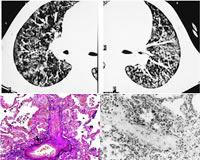

上期刊出了1例喘憋、肺水肿、肺动脉高压患者的病历简介,本期继续刊出针对该病例鉴别诊断的各路专家观点。

患者有肥胖、高血压、糖耐量异常和吸烟等危险因素,冠脉CT不除外冠脉病变,当时难以除外感染诱发的急性左心衰。尽管B型钠尿肽(BNP)水平升高支持心功能不全的诊断,但BNP并非心衰的特异指标。多次超声均显示心脏结构和收缩功能无显著异常;虽然E峰速度与A峰速度比值(E/A)>2,但肺静脉血流和二尖瓣环情况不支持左心舒张功能不全,且估测肺动脉舒张压、左房压及左室充盈压均不高。此外,经抗炎、强心、利尿(静脉托拉塞米80 mg/d)、扩血管、抗血小板、降脂及吸氧等对症治疗,患者体重在2周内下降8 kg,但喘憋症状进行性加重、胸部影像学结果未改善。

常见病导致的非心源性肺水肿?

考虑到患者血沉快、C反应蛋白(CRP)明显升高,无心肌缺血及器质性心脏病的证据,在充分给予针对心衰的治疗后肺水肿不仅未减轻反而加重,应除外其他导致喘憋、双肺片状影的非心源性疾病,如结缔组织疾病引起的肺间质、肺血管病变,以及肺栓塞,急性呼吸窘迫综合征(ARDS)等疾病。但患者无免疫疾病的临床表现,实验室检查也无异常发现,难以用常见疾病解释其整个临床过程 ......